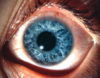

Quais são os achados clássicos da forma palpebral da ceratoconjuntivite primaveril?

Papilas > 1,0 mm predominando na conjuntiva tarsal superior

Sinal de Maxwell-Lyons - secreção mucosa acumulando-se entre as papilas

Fonte: AAO